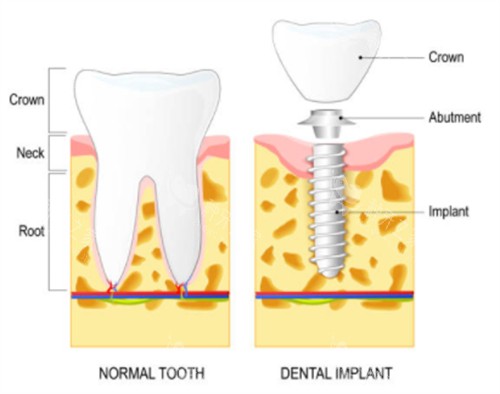

二、材质与设计

奥齿泰种植体的材质是其耐用性的重要确保。它采用纯钛材质,这种材质不仅重量轻,而且坚固耐腐蚀,能够长期保持稳定的性能。此外,奥齿泰种植体还采用了独特的多重微螺纹设计,这种设计使得植入更加顺利,植入后更稳定,成功概率更高。同时,种植体表面经过多孔纳米氧化钛技术处理,增强了生物活性,减小了排异性,更有效刺激骨细胞发育,加快稳定过程,提高存活率。